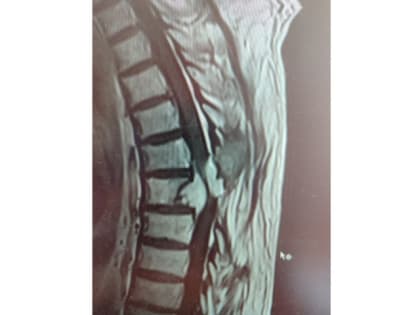

У жителя Балаково нашли опухоль, сдавившую позвоночник: история спасения

© Telegram-канал ГУЗ СО «Балаковская городская клиническая больница» Жителю Балаково провели сложнейшую операцию по удалению опухоли грудного отдела позвоночника, сдавившей спинной мозг.